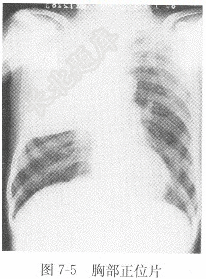

试题详情单项选择题男性,60岁,高热伴呼吸困难2天,X线影像见图7-5,X线诊断为( )。A、右上肺癌B、右上肺炎C、右上包裹胸腔积液D、右上肺结核正确答案:关注下方微信公众号,搜题查看答案热门试题剩余碱(BE)题见图6-4。 正常心电图检查气胸正常胸部正位片题见图6-11。CT检查血清尿酸(UA)测定题见图6-2。 硬膜下血肿血常规血浆纤维蛋白原(FG)泌尿系结石脑出血血清氢参考值血清总钙阵发性室上性心动过速原发性肝癌肝囊肿二氧化碳结合力(CO2CP)